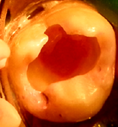

Paciente de sexo masculino de 23 años, con piezas 27 y 28 con caries profunda, ecosistema cerrado y cámaras amplias en análisis clínico radiográfico (figs. 4a,b). Se plantea tratamiento conservador en 27 y extracción en 28 ya que no ocluye con antagonista. En 27 se abre esmalte socavado, se elimina con cucharita la dentina necrótica reblandecida superficial, constatando ligera sensibilidad sin comunicación. En el análisis dentinario se observa dentina de color amarillo, blanda y húmeda, o sea con las características de una caries muy activa (Fig 4c).